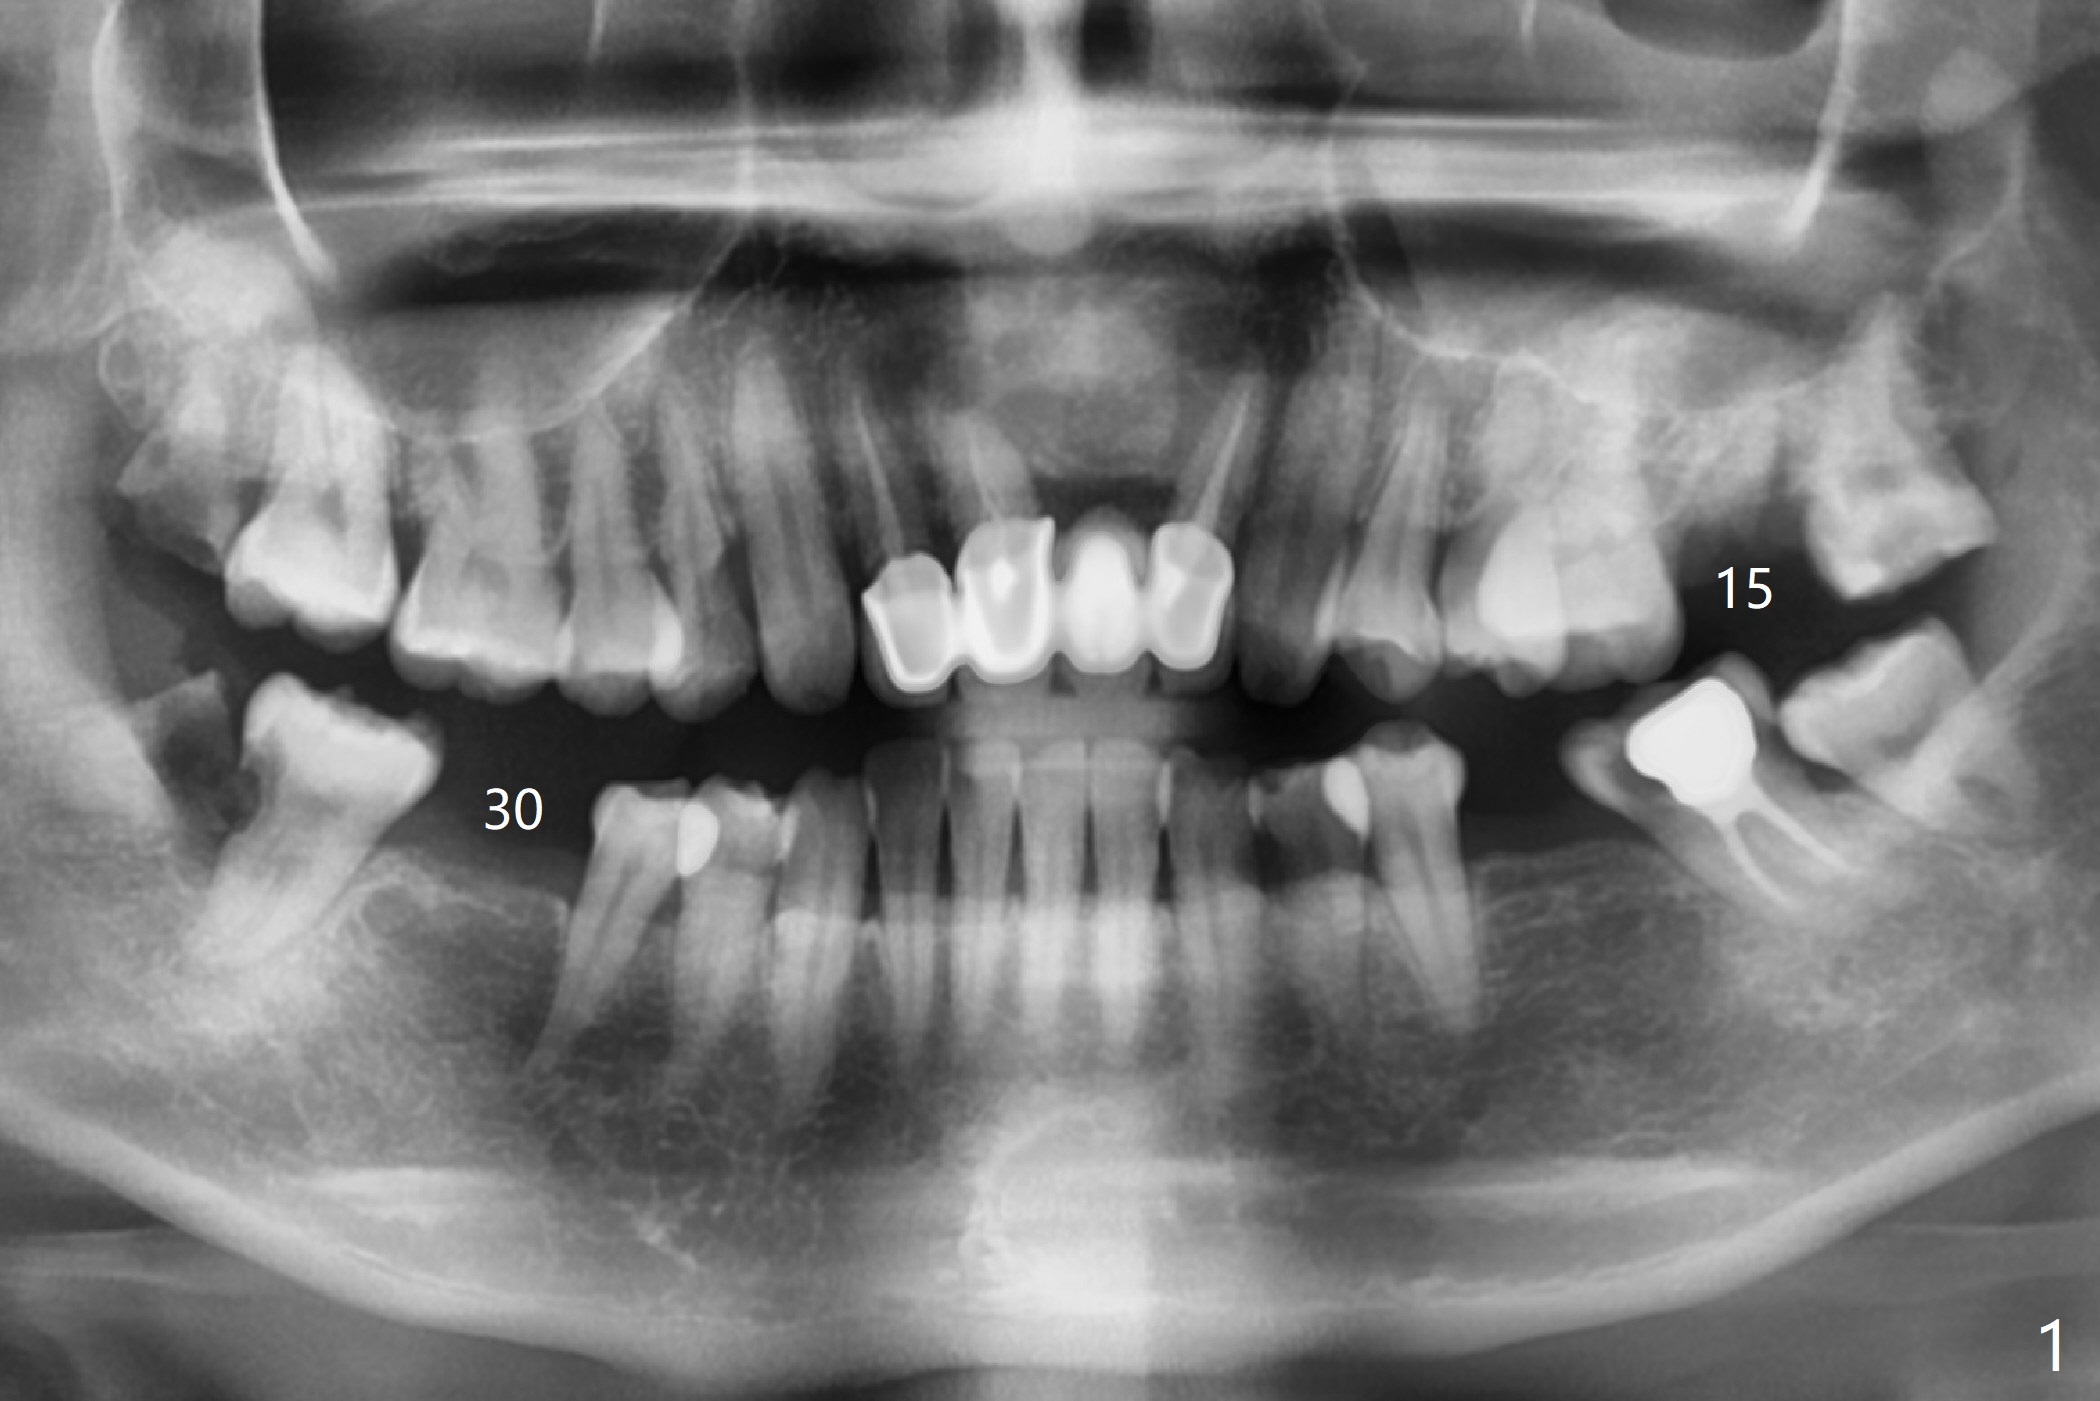

A 44-year-old woman is extremely nervous about dentistry. She presents to office with #15 infection (Fig.1). Since there is malocclusion on the left side (#13 cross bite, 14,18 supraeruption, and 17 and 18 mesial tilt) and she refuses orthodontic treatment, the tooth #15 will be extracted without implant before she leaves for China in 4 months. Guided implant at #30 will be placed first to show that the procedure is painless (Fig.2). In fact an appointment is made for #32 extraction and #31 composite or sedative filling, but she is reluctant to have them done.